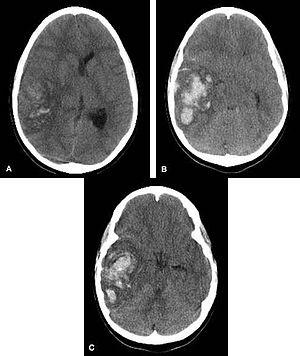

Multiple intraparenchymal hemorrhage.jpg

Multiple intraparenchymal hemorrhage

Intraparenchymal hemorrhage (IPH) is one form of intracerebral bleeding in which there is bleeding within brain parenchyma. The other form is intraventricular hemorrhage (IVH).

Intraparenchymal hemorrhage accounts for approx. 8-13% of all strokes and results from a wide spectrum of disorders. It is more likely to result in death or major disability than ischemic stroke or subarachnoid hemorrhage, and therefore constitutes an immediate medical emergency. Intracerebral hemorrhages and accompanying edema may disrupt or compress adjacent brain tissue, leading to neurological dysfunction. Substantial displacement of brain parenchyma may cause elevation of intracranial pressure (ICP) and potentially fatal herniation syndromes.